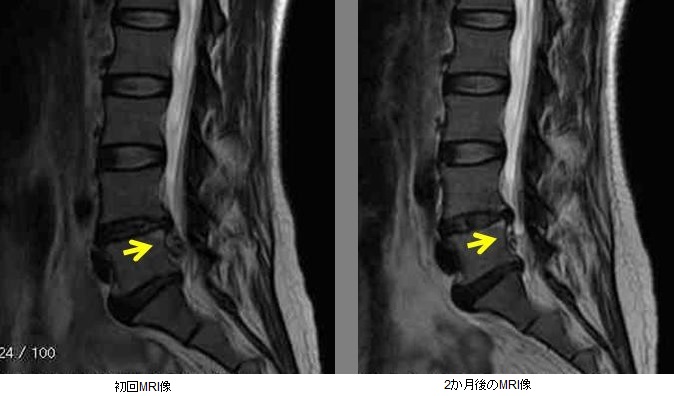

기본적으로 디스크는 자연스럽게 치유될 수 있는 질환입니다. 이 경우 치유란 증상이 소실된다는 뜻입니다. 근본적으로는 한번 디스크를 일으킨 디스크가 원래대로 복구·재생되지 않습니다. 그러나 탈출한 디스크가 축소되거나 소실될 수는 있습니다. 이 현상은 최근 MRI라는 검사를 경시적으로 반복함으로써 분명해졌습니다. 즉 디스크 진단을 받은 경우에도 사람의 몸이 본래 가지고 있는 치유 능력에 의해 디스크가 흡수되고 축소되어 증상이 완화되고 자연스럽게 치유될 수 있기 때문에 결코 비관적일 필요는 없습니다. 따라서 허리디스크로 진단되면 통증이나 마비 증상이 중증이 아니라면 2차에 언급하는 보존적 치료를 하고 일정 기간(몇 주에서 한 달 정도)은 증상 변화를 봐야 합니다. 누구나 피하고 싶은 수술적 치료를 서두를 필요는 없는 것입니다.